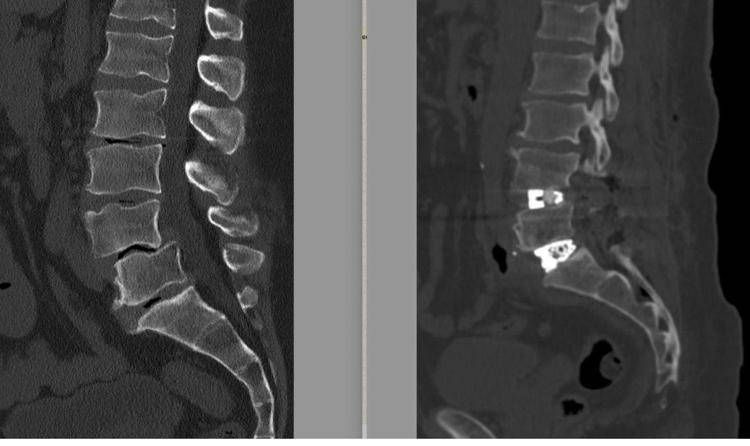

Al Tiberia Hospital di Roma, struttura di Gvm Care & Research accreditata con il Servizio sanitario nazionale, "è stato eseguito con successo un intervento di chirurgia vertebrale di alta complessità su un paziente di 55 anni affetto da una spondilolistesi L4-L5 e grave discopatia L5-S1, associate a un grave sbilanciamento dell'equilibrio sagittale della colonna vertebrale, utilizzando la tecnica Alif (Anterior Lumbar Interbody Fusion - artrodesi intersomatica con approccio combinato anteriore e posteriore) su entrambi i livelli. Una tecnica ancora poco diffusa in Italia, che richiede competenze elevate, ma che consente un recupero funzionale più veloce", descrive una nota. "La struttura romana - si legge - è polo di riferimento per la chirurgia vertebrale complessa e tra i pochi centri in Italia ad eseguire la tecnica Alif; questo intervento conferma il percorso di sviluppo di Tiberia Hospital come riferimento sul territorio per la chirurgia ad alta complessità".

La diagnosi era di spondilolistesi tra la quarta e la quinta vertebra lombare (L4-L5), una patologia degenerativa cronica caratterizzata dallo scivolamento progressivo di una vertebra sull'altra, associata a una discopatia del disco intervertebrale L5-S1. Nel tempo - sottolineano gli esperti - questa deformità determinava una compressione significativa delle radici nervose, provocando una sciatalgia bilaterale invalidante, con dolore irradiato agli arti inferiori che peggiorava in posizione eretta e durante le attività quotidiane e lavorative, compromettendo in modo rilevante la qualità di vita.

Un passaggio fondamentale nella pianificazione dell'intervento chirurgico - illustra la nota - è stato lo studio dei cosiddetti 'parametri spino-pelvici', effettuato su una radiografia dell'intera colonna vertebrale. Questi supportano il chirurgo vertebrale nella scelta dell'approccio chirurgico più corretto e della tipologia di impianti da utilizzare in base al grado di lordosi da ripristinare. "Oggi la chirurgia vertebrale non si limita a liberare i nervi o a stabilizzare un segmento ritenuto instabile - precisa il neurochirurgo e chirurgo vertebrale - ma punta a ricostruire un assetto posturale il più possibile fisiologico. Il mancato rispetto e, quando possibile, ripristino di questi parametri può portare nel tempo al fallimento del costrutto impiantato nella colonna vertebrale o alla prematura degenerazione dei segmenti della colonna adiacenti a quello trattato".

L'intervento è stato eseguito all'inizio di febbraio 2026 ed è durato circa 6 ore, riferiscono i sanitari. A 12 ore dalla chirurgia è stata eseguita una Tac addominale senza mezzo di contrasto per escludere eventuali complicanze legate all'accesso anteriore, mentre una radiografia in posizione eretta ha consentito di verificare immediatamente la qualità della correzione ottenuta. Il decorso post-operatorio è stato regolare. Il paziente si è risvegliato con un miglioramento sostanziale della sintomatologia sciatalgica e con un dolore limitato alle ferite chirurgiche, gestibile con comuni analgesici. In assenza di complicanze neurologiche o generali, è stato dimesso in seconda giornata post-operatoria. Rientrato a casa, il paziente prosegue il monitoraggio clinico con l'équipe di Chirurgia vertebrale di Tiberia Hospital. Nelle prime settimane, la riabilitazione consiste principalmente nella deambulazione e nella ripresa graduale delle attività quotidiane senza caricare la colonna.